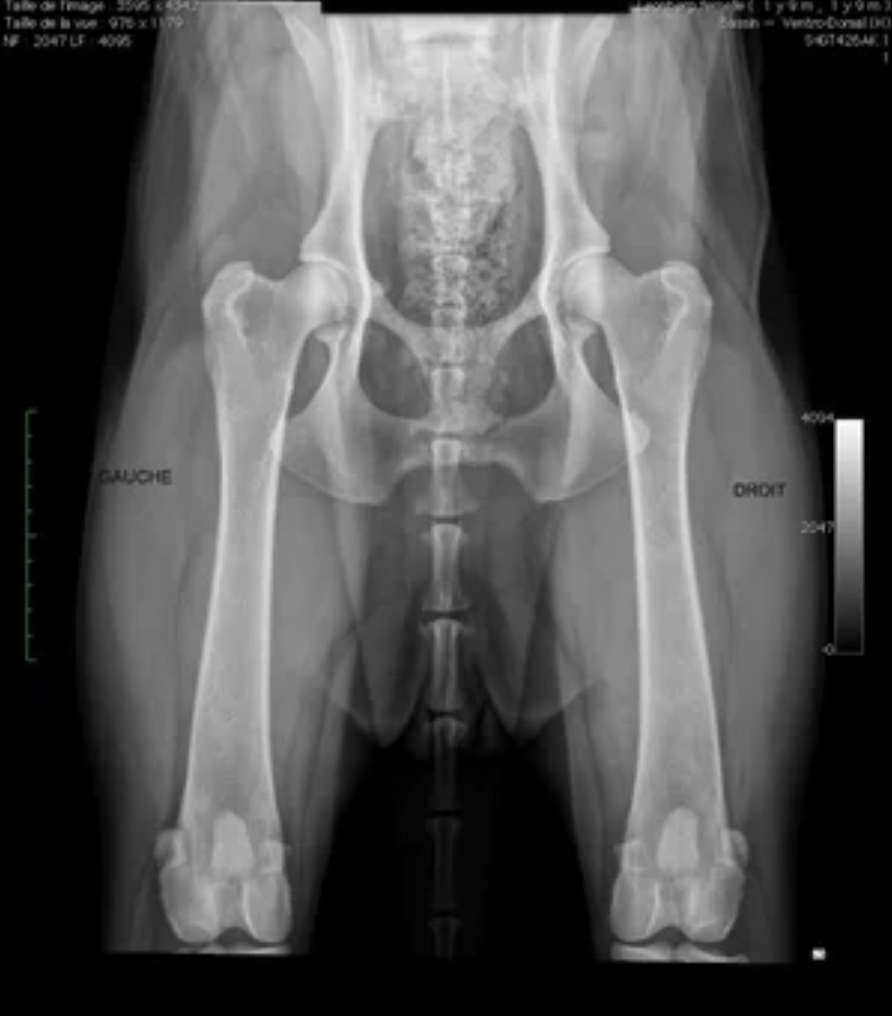

La radiographie : examen de référence

La radiographie est la méthode de référence validée scientifiquement. Elle est réalisée sous sédation ou anesthésie légère. Le relâchement musculaire est recherché. Ainsi, la position articulaire réelle est évaluée.

Les clichés sont réalisés selon des critères stricts :

-

bassin parfaitement symétrique,

membres postérieurs en extension complète,

centrage précis sur les hanches.

Source : Société centrale Canine.

Ce que le vétérinaire analyse à l’imagerie

Sur les clichés radiographiques, plusieurs critères précis sont évalués :

profondeur de l’acétabulum,

recouvrement de la tête fémorale,

sphéricité fémorale,

symétrie des deux hanches,

signes d’arthrose débutante.

Ces éléments objectivent la sévérité.

Ils orientent aussi la stratégie de prévention dysplasie chien.